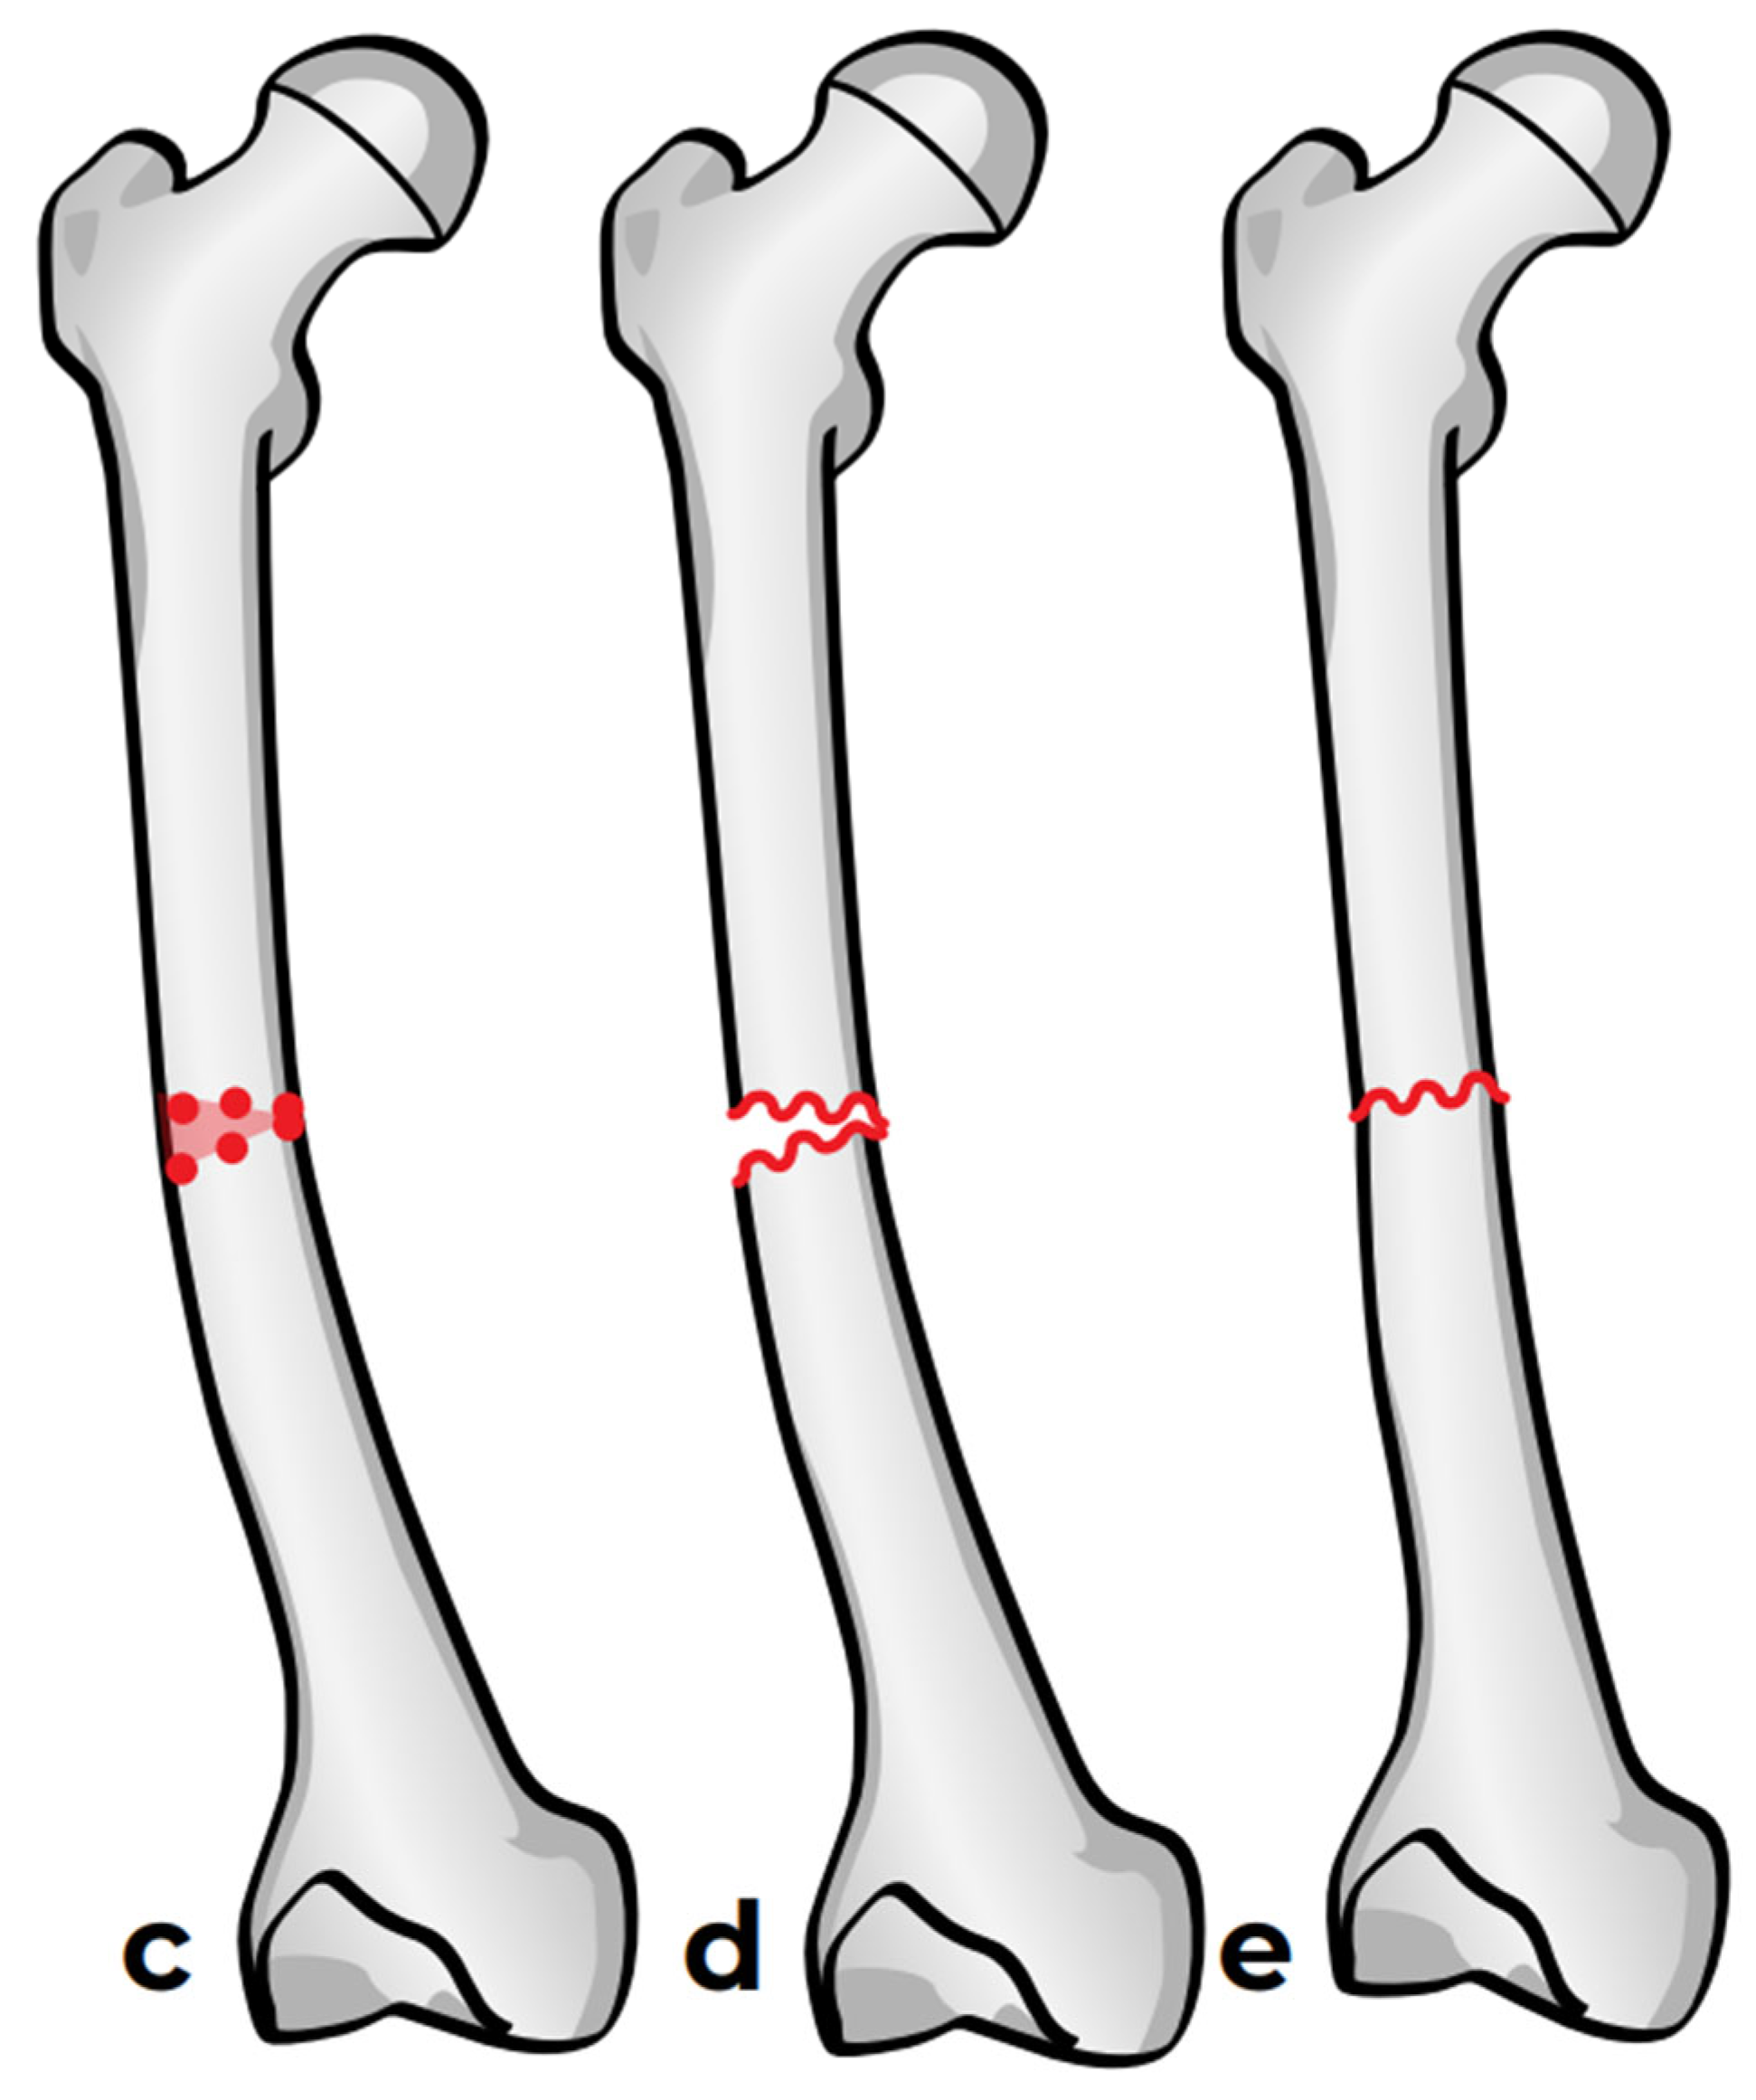

In the third case, a 16-year-old skeletally mature patient with OI was scheduled to undergo revision from FD rod to SLIM nail after presenting with pain due to stress fractures and wild deformity in his proximal right femur (Figure 11). The FD rod was removed, and then, using a piriformis entry point, access to the femur and proximal reaming was performed. There were two CORAs; the first CORA was identified in the subtrochanteric region, and a percutaneous osteotomy technique was performed to realign the bone, and then reaming was continued (Figure 12). The second CORA was identified, and another percutaneous osteotomy was performed, and the bone was cracked with a closed osteoclasis technique, and then reaming was continued in the distal segment (Figure 13). The SLIM nail was then inserted and had an excellent fit. The subtrochanteric region was under high stress, so a 2.7 Smith and Nephew EVOS plate to further stabilize the segment and control the rotation. Two screws were placed above and below (Figure 14). In this case, the indication for the use of the SLIM nail was the need to revise the existing telescoping FD rod in a skeletally mature patient to a solid nail. As the intramedullary canal was too small to accommodate a larger solid nail, a SLIM nail was used instead. The use of a plate as an adjunct to an intramedullary nail is also shown.

Figure 11.

Pre-operative X-ray showing right femur stress fracture.

Intraoperative X-rays showing the first CORA and alignment with the continuation of the reaming.

Intraoperative X-rays showing the second CORA and realignment with the continuation of the reaming.

Figure 14.

Post-operative X-ray showing SLIM nail and plate.